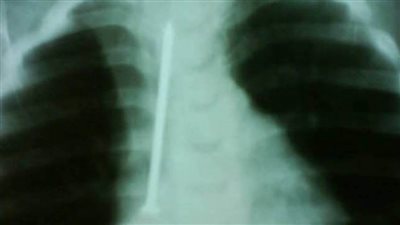

إنقاذ حياة طفلة ابتلعت مسمار 6 سم بمستشفى الأطفال التخصصى ببنها

السبت 25/أكتوبر/2025 - 11:46 ص